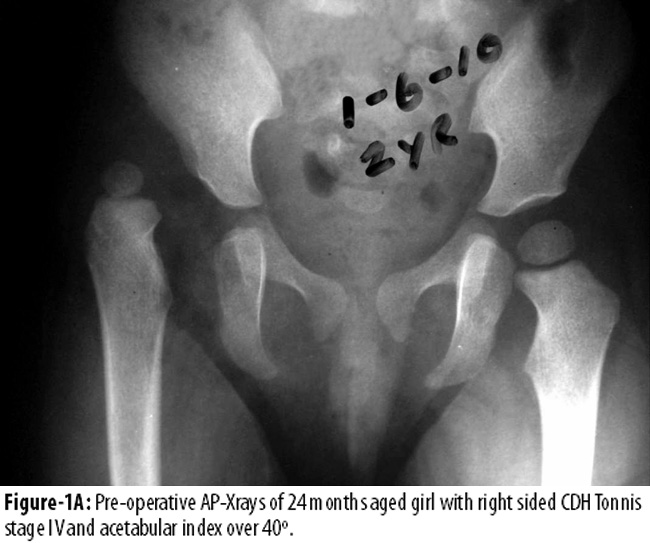

Figure-1 represents the height of dislocation at Tonnis level IV11 and acetabular index over 40° on right side compared to 18 degrees on normal side in a two year aged patient.